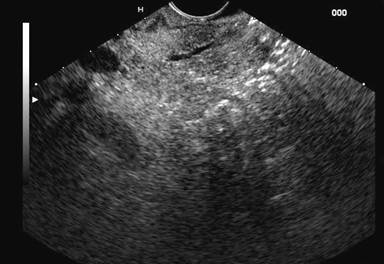

concluded that linear EUS is a

promising test for the diagnosis of pancreas divisum. In our experience also,

the diagnosis of pancreas divisum can be excluded if the pancreatic duct can be

followed from the major papilla to the pancreatic body or crosses the

endosonographic border between the ventral and dorsal pancreas (Figures 2 and 3).

Figure 2. Linear EUS:

pancreatic duct (PD) and common bile duct (CBD) identified at the papilla

resembling the stack sign obtained in radial EUS. |

Figure 3. Linear EUS:

pancreatic duct seen crossing the endosonographic border between hypoechoic

ventral anlage and brighter dorsal anlage. |